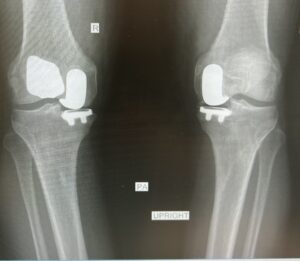

After years of battling lingering damage from repeated injuries, Lindsey reached a crossroads. Even the simplest daily movements became painful, and the rigorous training required for elite downhill competition felt out of reach. Ultimately, she underwent a partial knee replacement — a procedure that replaced only the damaged compartment of her knee while preserving healthy bone, ligaments, and natural motion.

The surgery relieved the relentless bone‑on‑bone pain that had limited her for years. As her strength returned, so did her confidence. Lindsey was able to train again without fear, rebuild power and stability, and ultimately return to compete at the highest level of the Olympic Downhill.

Her story demonstrated to the world that modern orthopedic advancements — including partial knee replacement — can restore not only daily comfort but also exceptional performance.

He has performed more unicompartmental (partial) knee replacements than any surgeon in Central Florida, offering patients a life‑changing alternative when full replacement is not necessary.